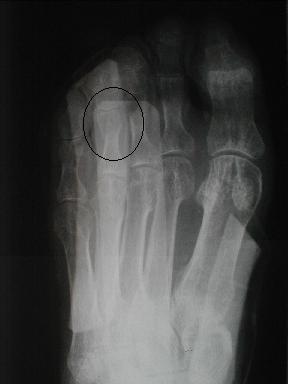

10月6日 受傷後96日目

10月13日

日常動作には支障なく経過良好にて治癒とす